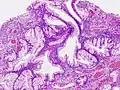

- Микроструктура полипов желудка

Полип фундальных желёз -